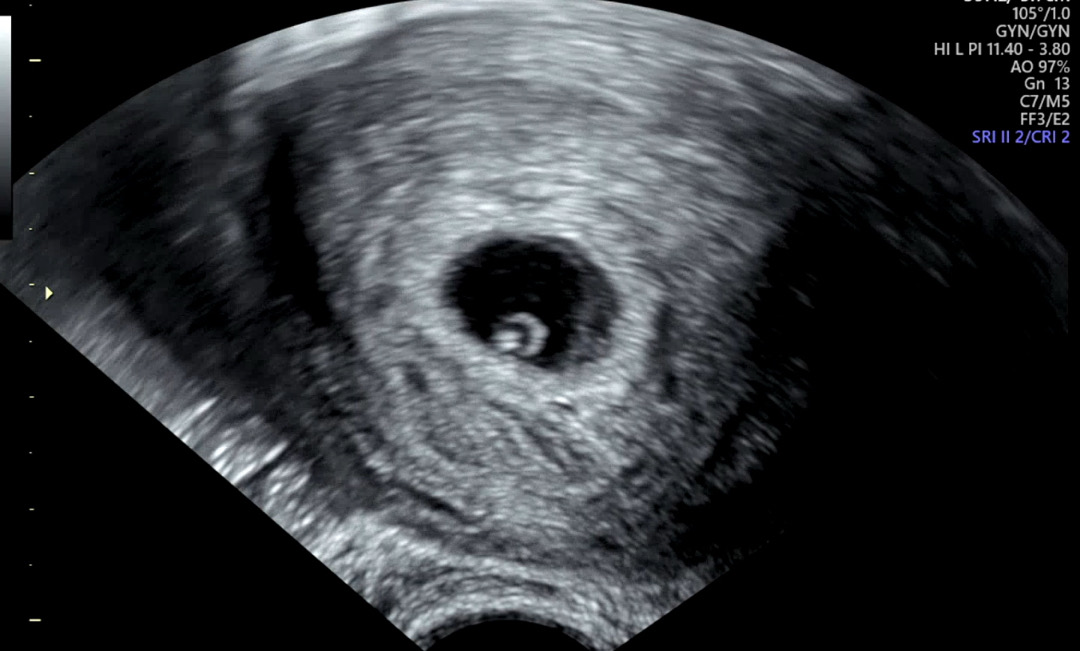

6주0일 난황보러갔다가 심소까지 듣고 왔어요!

5주2일차 아기집만 확인해서 고사난자일까봐 너무너무 불안했는데 (이전 이력이 있었어요ㅠㅠ) 6주0일차에 갔더니 아기까지 보여서 심소까지 들려주셨어요! 이제 막 생겨서 103bpm 정도라는데 다음주엔 더 빨라질거라고 걱정하지 않아도 된다고 하셨음에도 또 걱정인형이 되었어요😂 비슷한 주차에 초음파 보신 분들은 어땟는지도 궁금해요! 여기 있는 아가들 모두 건강하게 크기를!